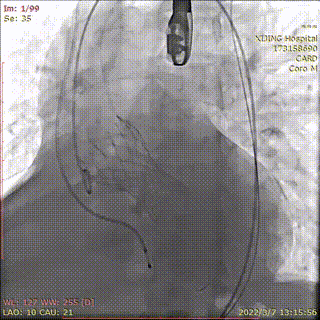

预置4.0*35mm冠脉支架左冠保护并根部造影

冠脉支架置于左主干并造影

烟囱支架扩张释放

造影显示左冠通畅

术后造影显示瓣膜位置理想,冠脉充盈正常